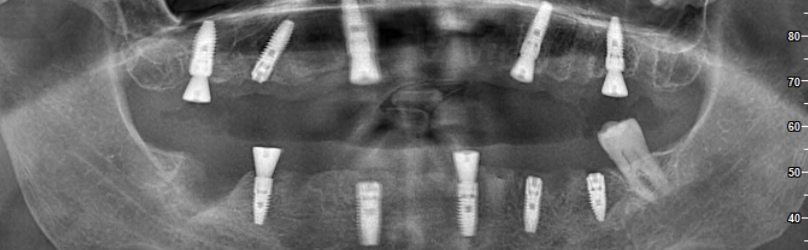

Dans les étapes ultérieures, vous pouvez regarder des vidéos sur la façon de placer des implants et de produire des prothèses. Ces vidéos visent à fournir une perspective informative à nos patients en montrant chaque étape du processus. Chaque étape est réalisée minutieusement par nos médecins experts.

Une fois le traitement terminé, vous pourrez visionner nos entretiens avec nos patients et entendre leurs expériences. Ces entretiens, qui racontent comment leur qualité de vie s’est améliorée en peu de temps et la valeur ajoutée du traitement implantaire à leur santé, seront une source d’inspiration pour nos autres patients.